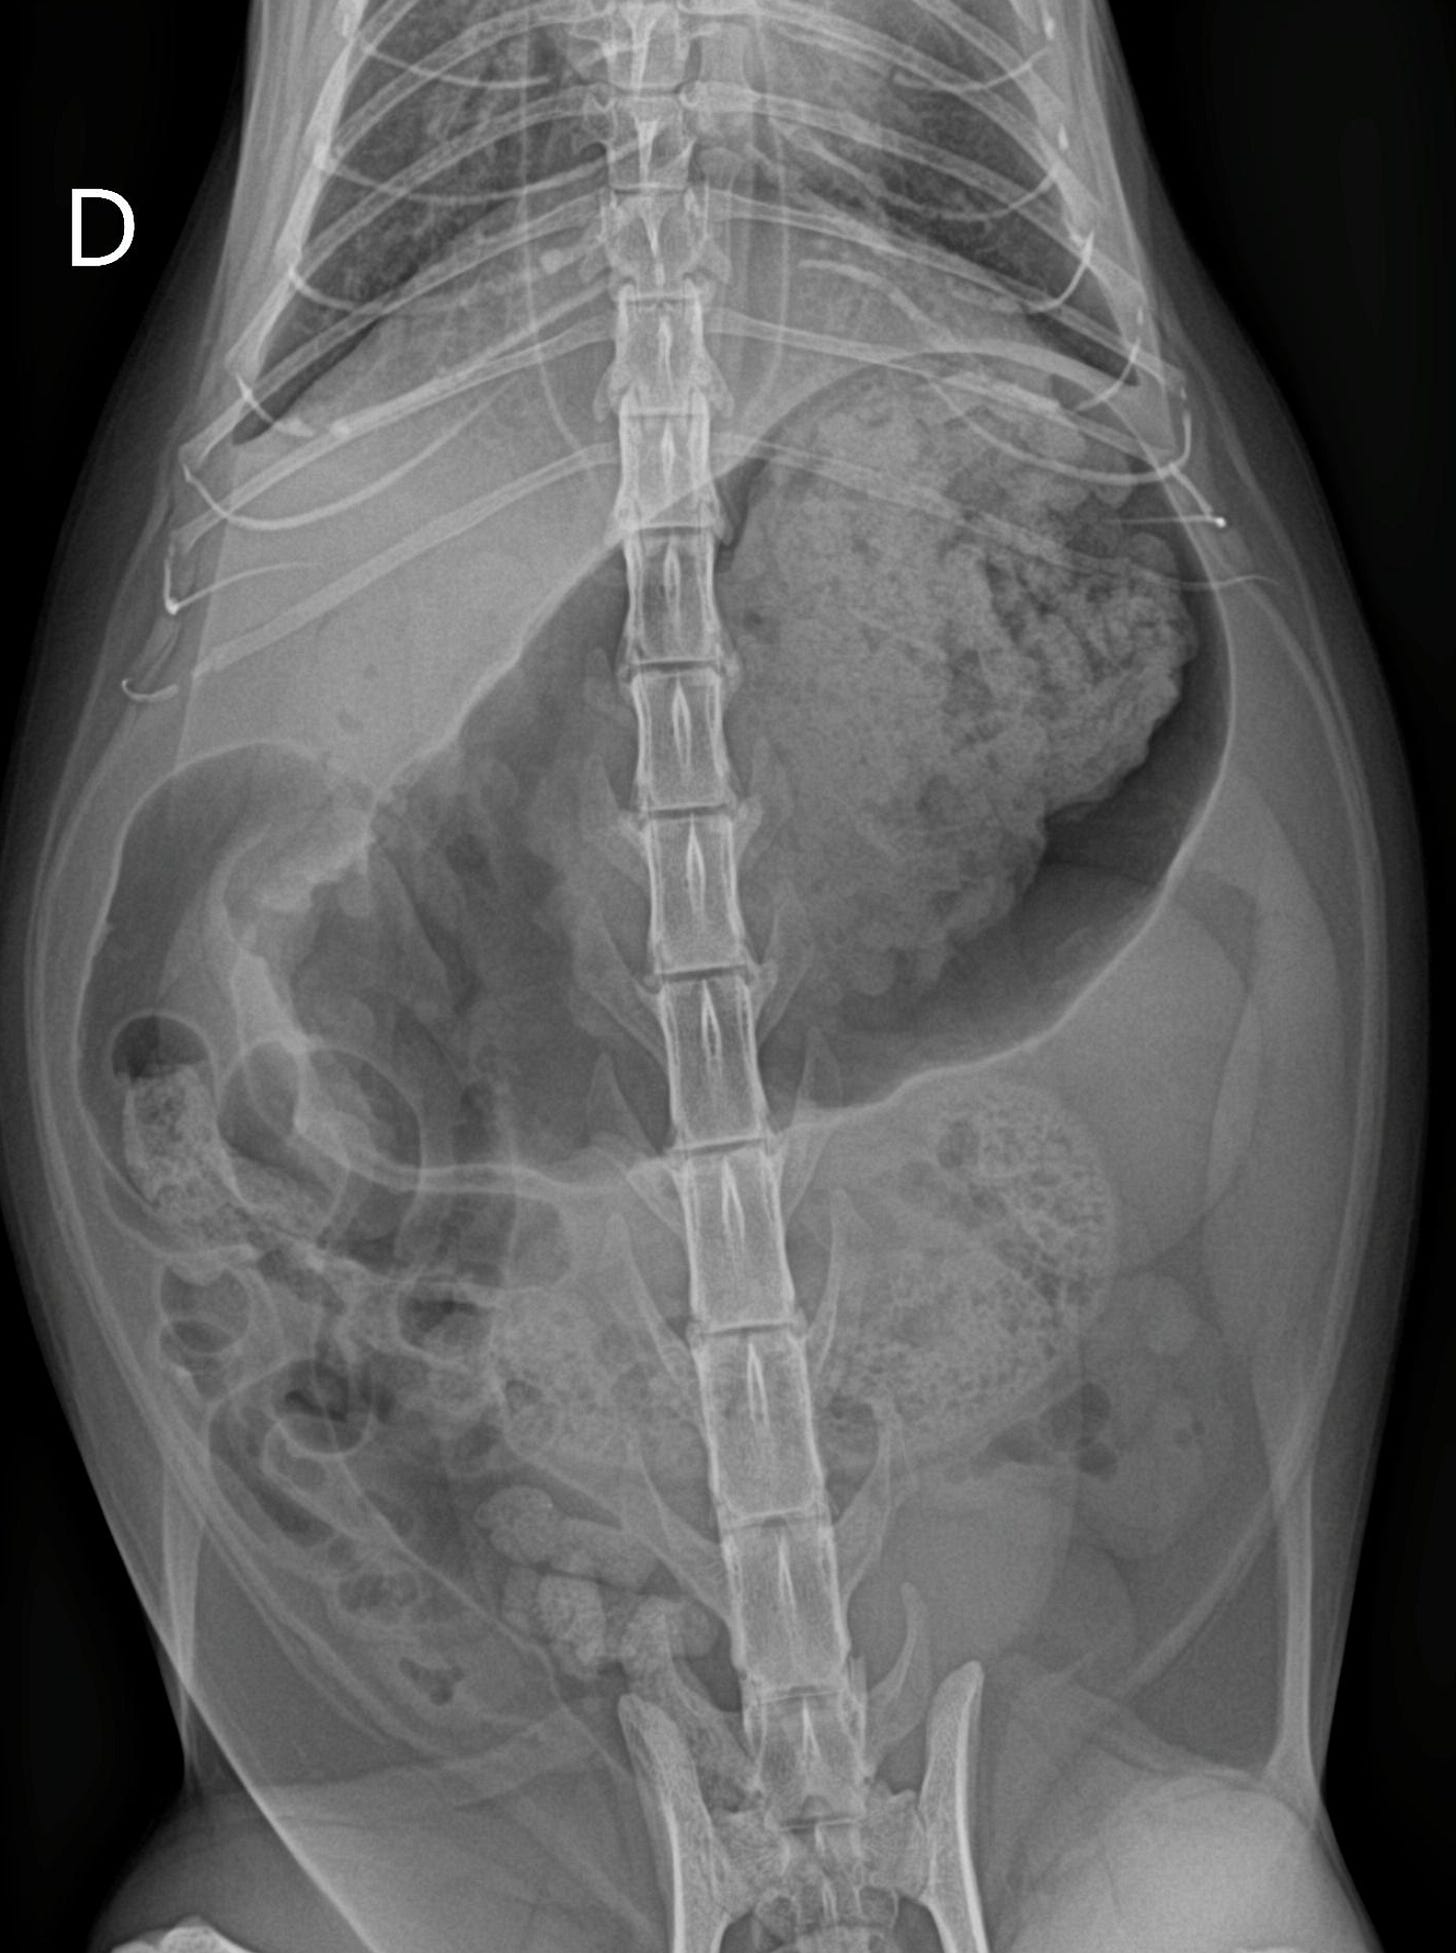

Hacemos un pequeño paréntesis. Arya presentó la semana previa a esta consulta con signos digestivos más acusados (vómitos / regurgitación). Esta eran sus radiografías, donde si no conociéramos el caso podríamos sospechar de un proceso digestivo obstructivo (puedes apreciar incluso megaesófago en la porción visible):

Estas imágenes en combinación con la patología respiratoria de Arya ilustra un bonito ejemplo de “síndrome aerodigestivo”. Recordemos que este síndrome describe la interacción patológica entre el tracto respiratorio superior y el tracto digestivo superior (faringe, laringe, esófago).

En gatos, cuando existe una estenosis nasofaríngea, se puede producir una disfunción aerodigestiva secundaria, ya que las alteraciones en el flujo aéreo nasal y faríngeo modifican la fisiología normal de la deglución, la presión intratorácica y la coordinación respiratoria-digestiva.